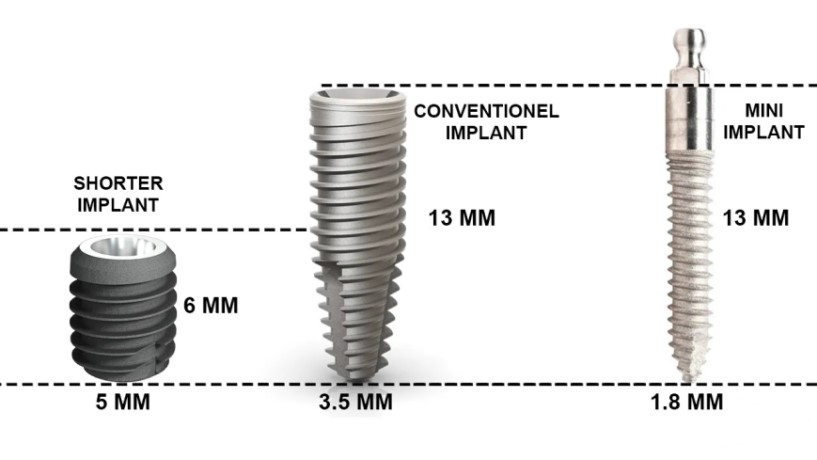

ایمپلنت کوتاه در ونک نوعی ایمپلنت دندانی است که طول آن معمولاً کمتر از ۸ میلیمتر است. در حالی که ایمپلنت های استاندارد طولی بیشتر دارند و برای کاشت آن ها به ارتفاع استخوان بیشتری نیاز است. طراحی ایمپلنت های کوتاه به گونهای است که بتوانند در شرایطی که استخوان کافی وجود ندارد، عملکردی مشابه ایمپلنت های معمولی ارائه دهند.

در گذشته تصور میشد هرچه طول ایمپلنت بیشتر باشد، دوام آن هم بالاتر خواهد بود. اما مطالعات جدید نشان دادهاند که کیفیت طراحی و سطح ایمپلنت، همراه با مهارت جراح، میتواند موفقیت ایمپلنت های کوتاه را به سطحی قابل اعتماد برساند. به همین دلیل این نوع درمان امروزه بهعنوان یک روش علمی و کاربردی شناخته میشود.

تفاوت ایمپلنت کوتاه با ایمپلنت استاندارد

1. طول و طراحی: مهمترین تفاوت در طول ایمپلنت است. ایمپلنت های استاندارد به ارتفاع استخوان بیشتری نیاز دارند، اما ایمپلنت کوتاه در استخوان های کمارتفاع هم قابل استفاده است.

برای انتخاب بهترین روش درمان، شناخت تفاوتها و شباهت های ایمپلنت کوتاه و ایمپلنت استاندارد اهمیت زیادی دارد. هر دو روش با هدف جایگزینی دندان های از دست رفته استفاده میشوند، اما شرایط بیمار و وضعیت استخوان فک تعیینکننده انتخاب نهایی است.

۱. طول و طراحی

- ایمپلنت معمولی: طول بیشتر از ۸ میلیمتر دارد و برای کاشت آن به استخوان بلند و محکم نیاز است.

- ایمپلنت کوتاه: طول کمتر از ۸ میلیمتر دارد و برای بیمارانی با ارتفاع استخوان کم طراحی شده است.

۵. طول عمر و موفقیت درمان

- ایمپلنت معمولی: سالهاست امتحان خود را پس داده و میزان موفقیت آن بالاست.

- ایمپلنت کوتاه: با وجود اینکه مدتزمان کمتری از معرفی آن گذشته، مطالعات نشان میدهد در شرایط مناسب موفقیتی مشابه دارد.